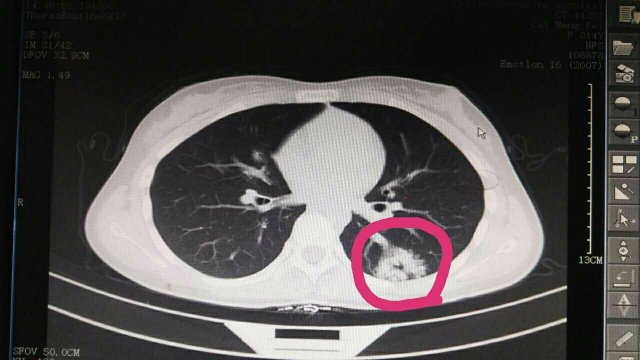

蔡**,女,14岁因“反复头晕3年余”,求诊福州及莆田各三级医院,做过很多辅助检查,均未确诊,于2017-2-26日就诊我院门诊,接诊是我院儿科林富医师,经过认真仔细查体,发现患儿左侧肩胛骨可闻及Ⅱ-Ⅲ/Ⅵ级收缩期杂音,为明确诊断,即刻请我院庄姞副主任医师(原莆田市第一医院NICU主任)会诊,查胸部CT发现左肺下叶背段血管畸形。庄姞副主任医师告诉我们,部分型肺血管畸形如果不认真查体是很难查体的到,年轻医师能如此仔细查体,确诊多家医院未确诊的疾病,不得不对林医生竖起大拇指,通过此次经历,可见临床医生必须熟练掌握临床三基的重要性。